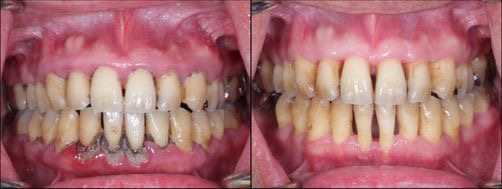

全顎的にインプラント治療を行った症例

歯周病治療前と治療後の比較